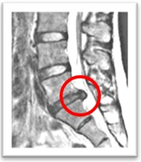

(背骨を横から見ています)

診断には、症状や身体検査、画像検査(MRIなど)が用いられます。

一般的に腰椎ヘルニアの診断には、MRIが最も適しています。

MRIは、腰椎の椎間板や神経根を非常に詳細に撮影することができます。